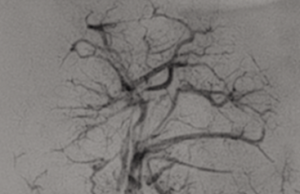

New embolic device demonstrates superior vessel filling in tumour models

Fluidx Medical disclosed study results examining extent of vessel filling using the GPX embolic device compared to microspheres, a common treatment for many types...

A novel embolization device in the interventional oncology space—the GPX embolic device (Fluidx Medical Technology)—has successfully been used in a patient to therapeutically devascularise...